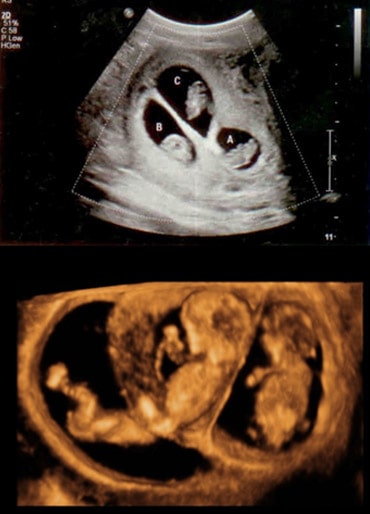

Foetal reduction

IVF is often associated with the chances of having twins or triplets. Such pregnancies can be very challenging and associated with complications during pregnancy as well as childbirth. Foetal reduction is the procedure of selective reduction of one or more foetuses during early pregnancy, to allow a lesser number of foetuses to continue till term. It helps in reducing the complications associated with multiple pregnancies. It’s a safe procedure, and the chances of complications are very low. However, decision making can be emotionally challenging.

It is done under general anaesthesia. The foetuses are localised with an ultrasound probe through the vagina. Then, a small needle is used to inject a special drug which quickly stops the foetus’s heart.

Infection after foetal reduction is rare and precautions are taken to reduce the chances of infection. A small number of women can miscarry after the procedure.